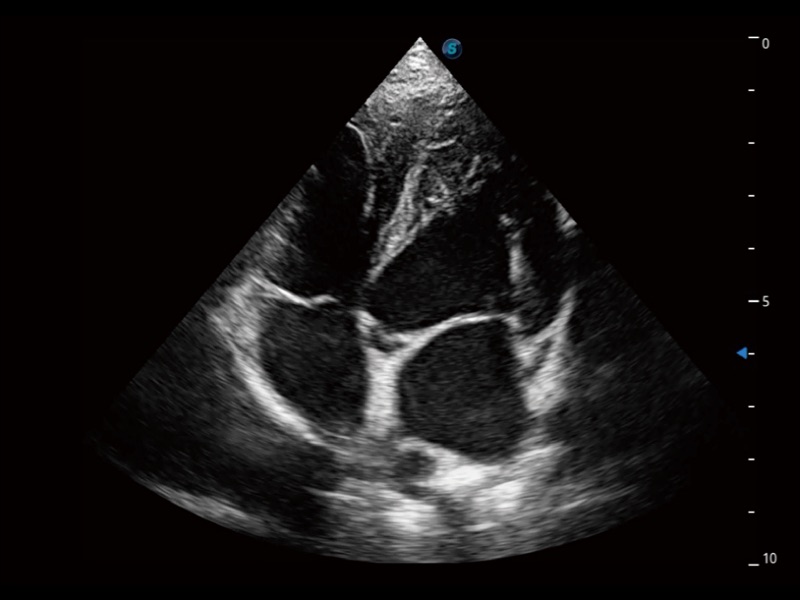

通過360度任意調(diào)節(jié)3條M型取樣線,在同一心動(dòng)周期上觀察心臟不同位置的運(yùn)動(dòng)曲線,得到準(zhǔn)確的心功能測(cè)量數(shù)據(jù),有效評(píng)估心肌運(yùn)動(dòng)及左心室功能。